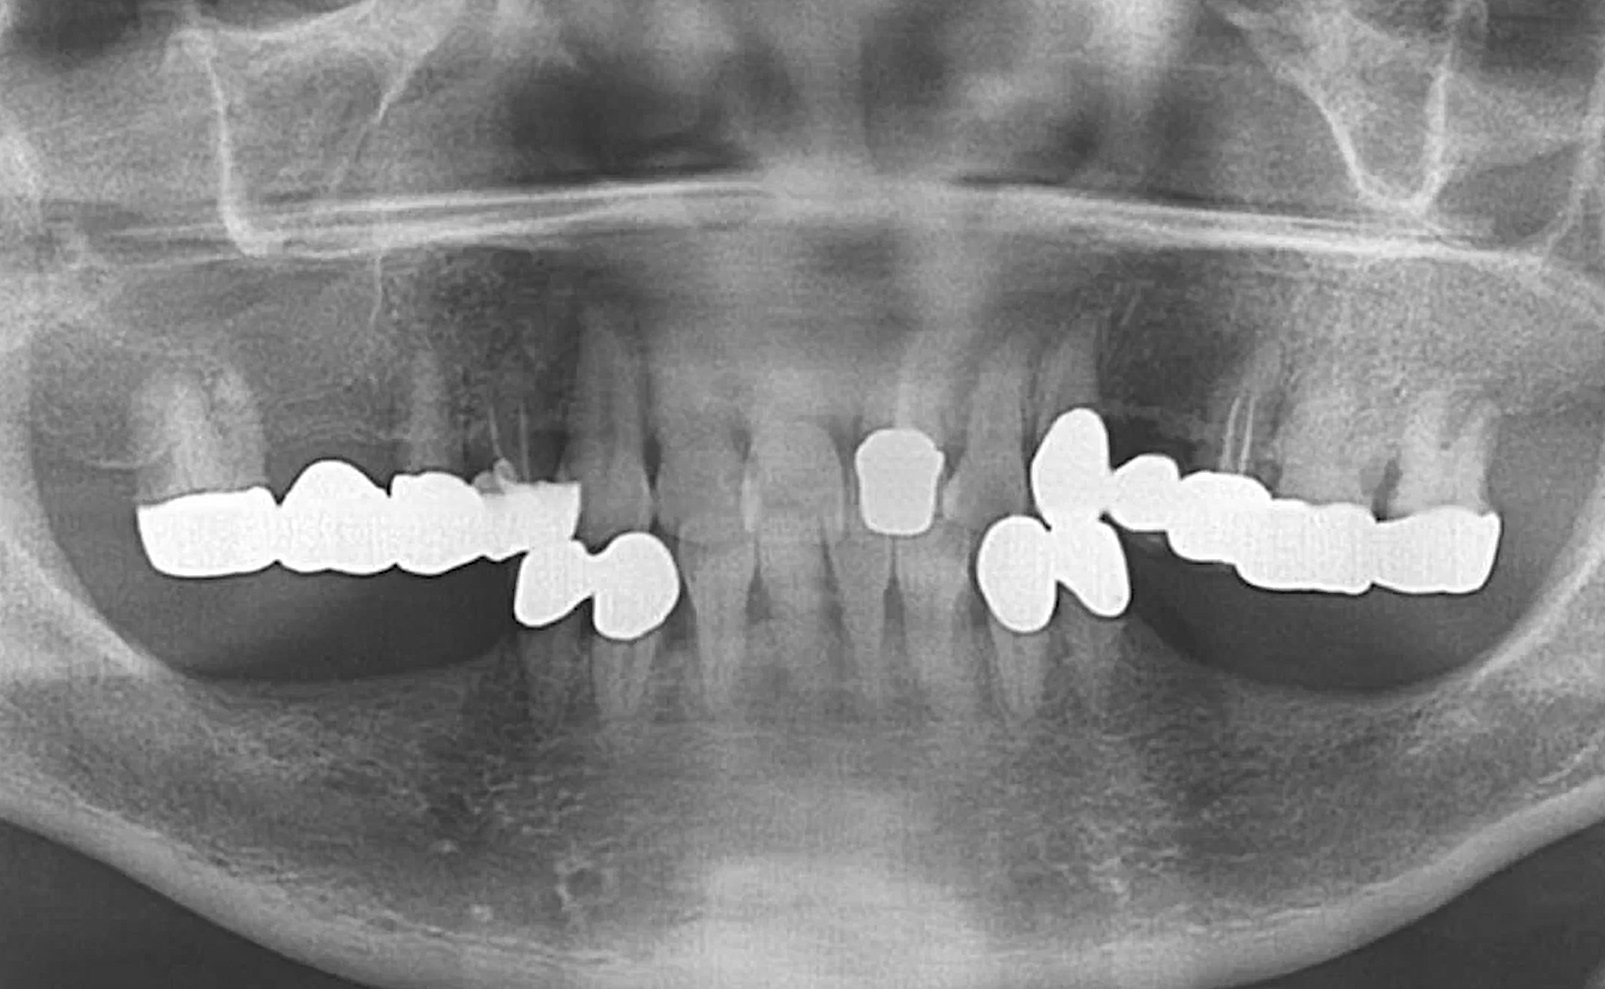

Root Membrane with R2GATE

Dr. Konstantinos Siormpas,Aesthetic Zone,Immediate loading,Digital,Bone regeneration,Maxillary Anterior,#12,#21,#23,Implant Placement,Guided surgery,Immediate loading,Flapless,Root Membrane,GBR,AnyRidge,MEGA ISQ,Root Membrane Kit,Video